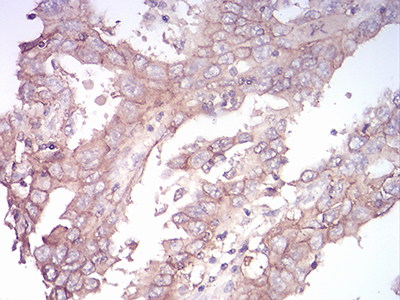

图片:

Immunohistochemical analysis of paraffin-embedded human bladder cancer tissue using anti- SPHK2 antibody. Counter stained with hematoxylin.